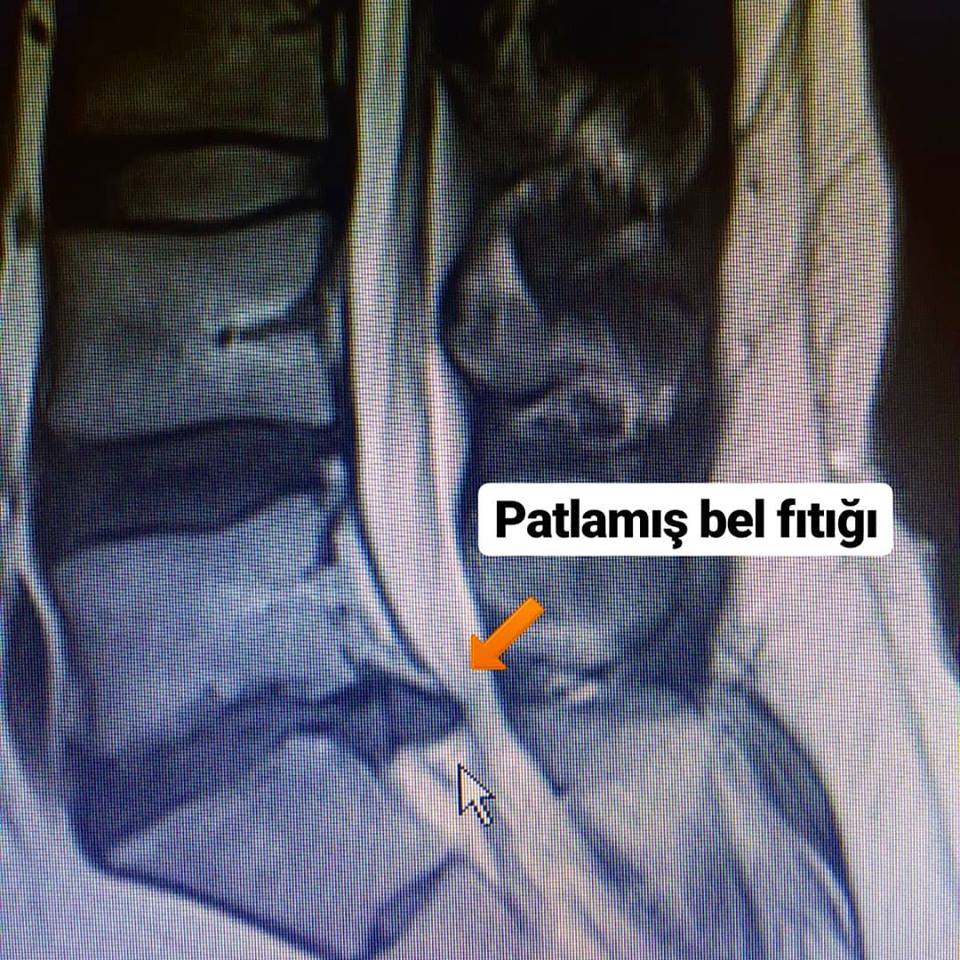

Bel fıtığı patlaması, bel bölgesinde olan omurlar arasındaki diskin dışında bulunan sert tabakanın yırtılmasıyla oluşur. Tabakanın yırtılmasıyla diskin içinde bulunan yumuşak madde dışarıya çıkarak, omuriliğe ya da sinir köklerine baskı yapar ve dolayısıyla ağrıya beden olur. Ağrı belle birlikte bacaklara yayılım gösterir.

Bu durum MİKROCERRAHİ ile tedavi gerektirir.